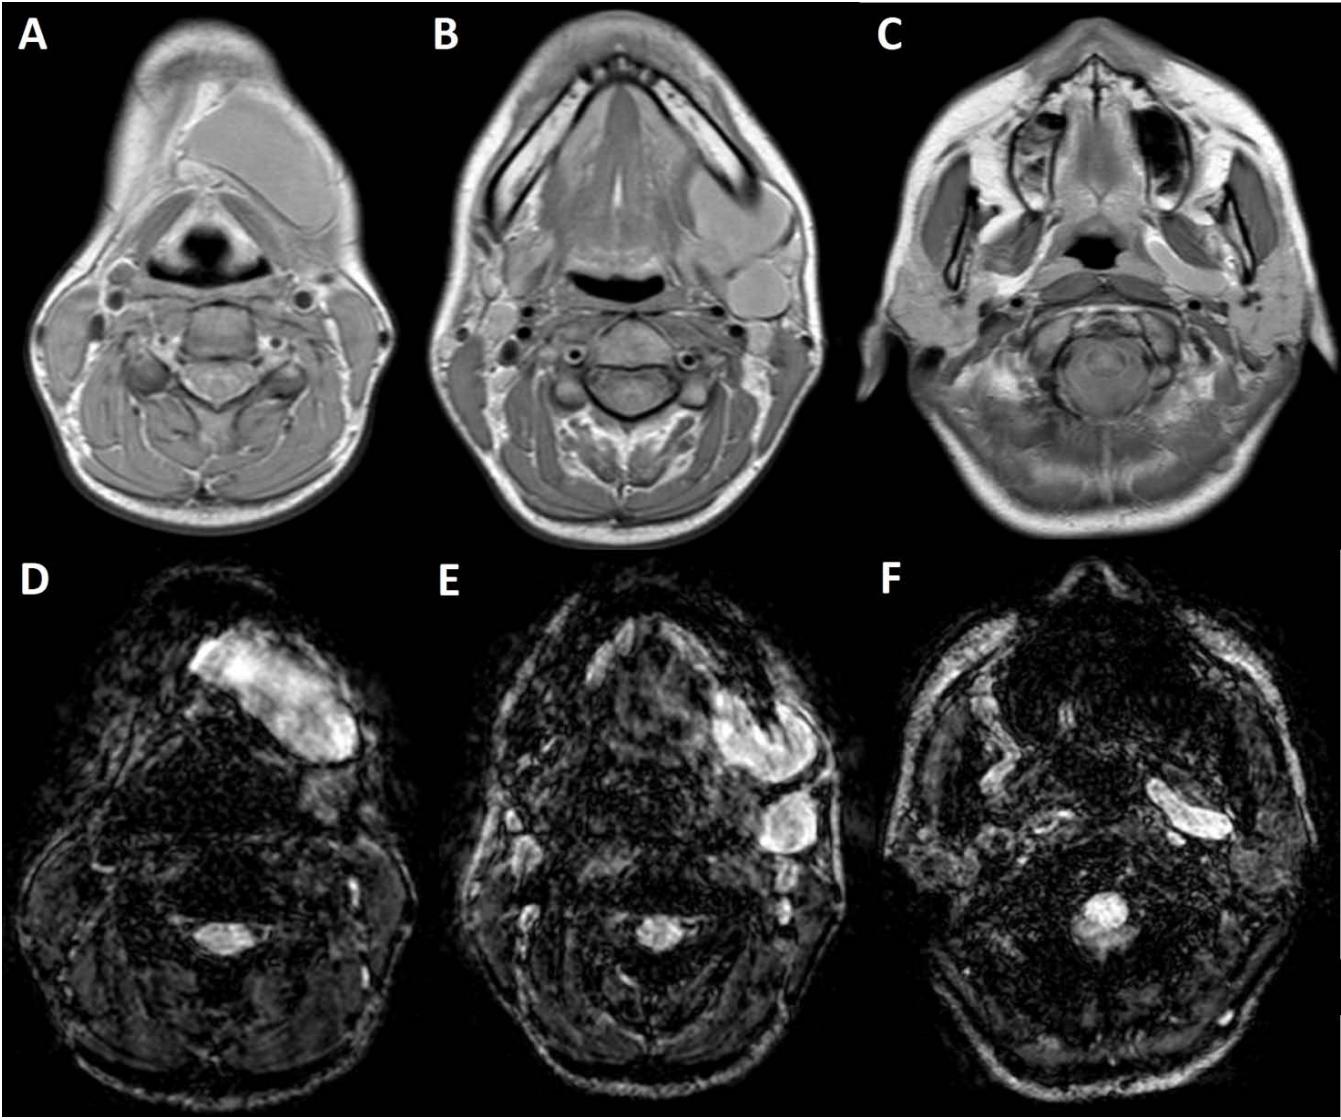

Figure/Patient 4

1. A 7 year-old girl presenting with a tumefaction at the level of the left latero-cervical region. MRI scans show a subcutaneous lesion occupying the left submandibular, parotidal, para-pharyngeal and part of the masticatory spaces. The lesion appears slightly hyper-intense on T1 (A-C) and markedly hyper-intense on T2 (D-F) scans. Diagnosis of cystic lymphangioma is done.

2. The same patient undergoing two different sessions (A-D and E-G, respectively) of sclerotherapy with absolute ethanol. An 18-G needle is introduced into the lesion and about 10 cc of citrine-turbid fluid are aspirated (B and F). Then, 5 cc of ethanol are injected and the patient is mobilised in order to distribute the SA throughout the lesion (D and G). The patient is dismissed and a one-week antibiotic therapy is prescribed.